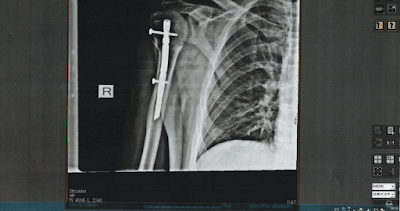

I tried to roll over, that was a bad idea as I rolled on the arm I landed on, that hurt a little. Ok, roll over in the other direction and as I slowly rose to my feet I knew my arm was hanging down. No problems, it was an impact so I expected it to be sore. It may have been dislocated, I accepted that, they may have to pop it back in. The x-rays told a different story though, I had to fly down to Johannesburg for some surgery. That involved a pin in my arm, some stabilisation and I was ready to return to work.

Sure, a year on and my arm still feels pain. I had limited movement so my rehab was pretty intense. Some of the exercises came from the hospital physio, some were my own but I knew I had to push on. I was warned if I couldn’t get movement they would put me back under and do it for me – that was pretty good motivation. I did my exercises daily, pushed through the pain and got my mobility back. I am back participating in sport, I ride my bike, run, sail and I am trying to get a decent weights program going.